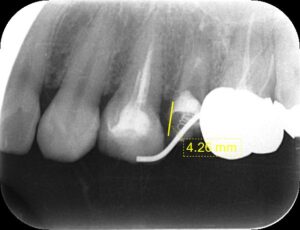

外傷といわれる転倒や衝突など。また、深い虫歯で歯が折れてしまい、歯肉から歯が見えない状態だと通常では抜歯となってしまいます。

その状態でも歯を残せる唯一の治療が救歯MTMです。 いわゆる歯根挺出やエクストルージョンといわれている治療方法です。

健康な歯質が骨内にあれば、それを矯正治療で引っ張り上げて、

健康な歯の部分を歯肉の上に引っ張り出して、その根の治療、土台を作り、硬いセラミックで歯を覆い、歯を温存する治療方法です。